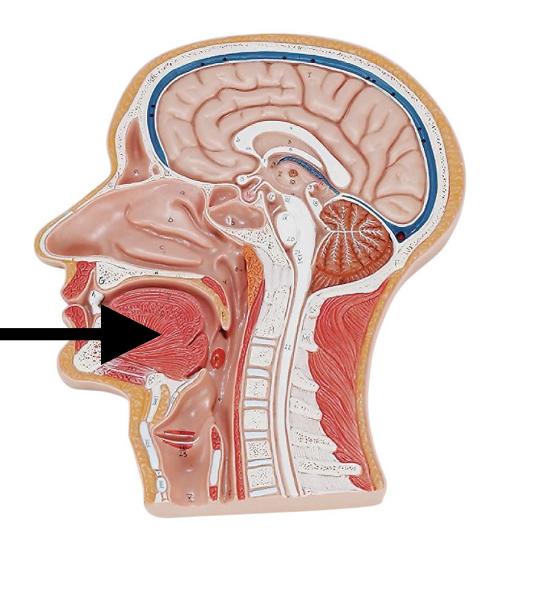

Epiglottis

Esophagus

Hard/soft palate

Inferior/middle/superior concha (s.) conchae (pl.)

Internal/external/common carotid artery

internal/external/common jugular vein

Larynx

arrow

Nares

Nasal Cavity

Nasal septum

Naso/oro/laryngo-phraynx

Oral Cavity

Paranasal sinuses

Parotid gland

Sublingual gland

Submandibular gland

Tongue

Trachae

Uvula

Vertebral artery

Vestibule (of nasal cavity)

Vocal folds (=vocal cords)